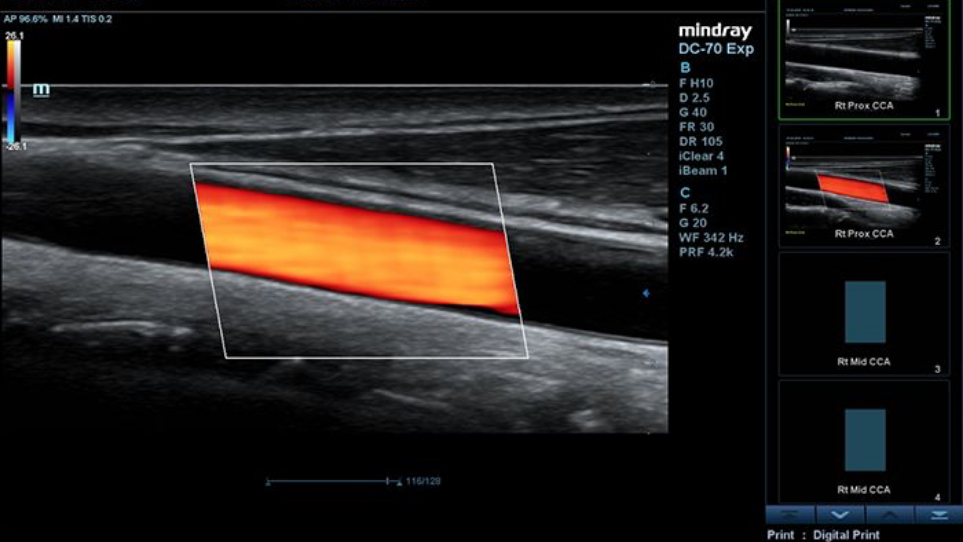

Some say that you can't have it both ways. When it comes to an ultrasound system, one has to choose between superior speed and optimum images. Yet Mindray begs to differ. Committed to advancing healthcare technologies, the innovator has been striving to deliver both efficiency and confidence in clinical diagnosis, in an exceptionally user-friendly manner.

One of Mindray's essential approaches to strike a perfect balance between speed and precision is eXceptional Intelligence, which is also the second component of X-Insight’s “3X” strategy.

Based on in-depth research into clinician's usage patterns and real-life clinical cases, Mindray develops a profound understanding of sonographers' crucial needs. The combination of the insights with cutting-edge technologies endows X-Insight with the ability to function intelligently, taking ultrasound imaging performance to the next level.

Keeping pace with this era of smartness, the innovative solution provides intelligent exams throughout the entire workflow, from plane acquisition to image optimization, and from calculation to exam protocol, with rich tools such as Smart Planes CNS, Smart Face, Auto EF, iWorks and more, improving scanning efficiency while ensuring accuracy and consistency.